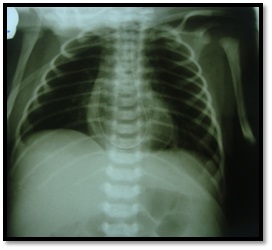

Physical

examination revealed slightly tachypnea

(respiratory rates=30-40 per minute).Other

sites had no problem. Arterial blood gas and electrolytes were normal .NGT was

inserted for gastric decompression and then we requested for him Thoraco-abdominal

X-ray (Figure 2).